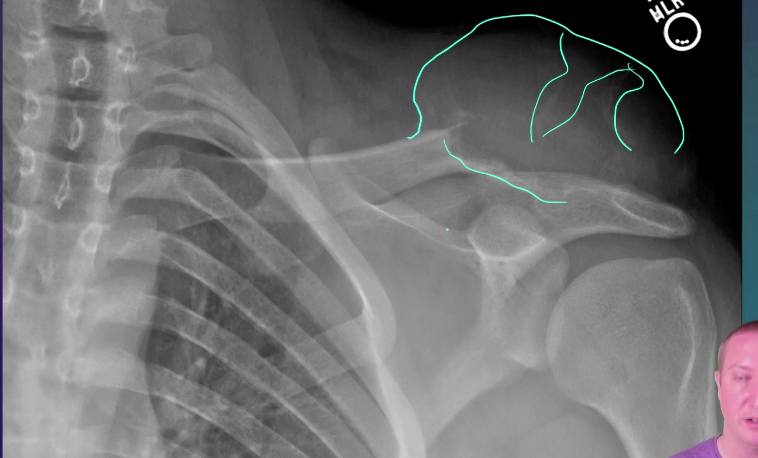

Posterior Dislocation

Dr Henry Knipe◉◈ and Radswiki◉ et al.

The trough line sign is a sign of posterior shoulder dislocation on AP shoulder radiograph.

Pathology

In a posterior dislocation, the anterior aspect of the humeral head becomes impacted against the posterior glenoid rim. With sufficient force, this causes a compression fracture on the anterior aspect of the humeral head. This compression fracture is analogous to the Hill-Sachs compression fracture seen with anterior shoulder dislocation of the glenohumeral joint.

Radiographic features

Plain radiograph

Frontal radiographs reveal two nearly parallel lines in the superomedial aspect of the humeral head.